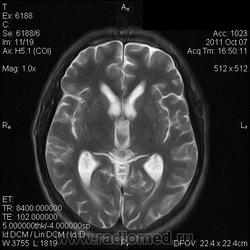

на МРТ - Определяется скопление крови в препонтинной цистерне, в проекции супраселлярной цистерны, в кортикальных бороздах полушарий головного мозга,  в проекции краниоспинального перехода. Выявляется горизонтальный уровень крови в задних рогах боковых желудочков. Боковые, третий желудочки резко расширены. Определяется перивентрикулярное повышение интенсивности сигнала от белого вещества головного мозга. Срединные структуры не смещены. Кортикальные борозды умеренно сглажены. Сильвиев водопровод прослеживается на всем протяжении. Отмечается смещение дна третьего желудочка каудально, с резким уменьшением размеров супраселлярной цистерны; базальные цистерны уменьшены в размере.

В проекции базальной артерии определяется аневризма размером до 4х6 мм.

Я не вижу участки скопления крови, а можно стрелочками указать, для особых не опытных ))) И аневризму стрелочкой пожалуйста. И все таки что за режим последней аксиальной? Tirm ( flair) ? Задние рога боковых желудочков мне не нравятся - но не ужели так кровь у вас видна ?

Мне напоминает FLAIR. В желудочках уровни крови и белое по субарахноидальным щелям тоже кровь. Аневризму тоже не вижу. Может долихоэктазия, если смотреть на сагитталы. Мелковато для меня, наверное.

А почему если это кровь то на т1 она не гиперинтенсивная, и на т2 она нет изменения сигнала? Гиперинтенсивный сигнал на FLAir в субарахноидальных я б подумала что глиозные изменения, но опять же я не вижу изменений на т2 ви. Или правда мелковато и мне не видно? Извините заранее я не спорю с заключением, просто пытаюсь разобраться - заодно и научиться